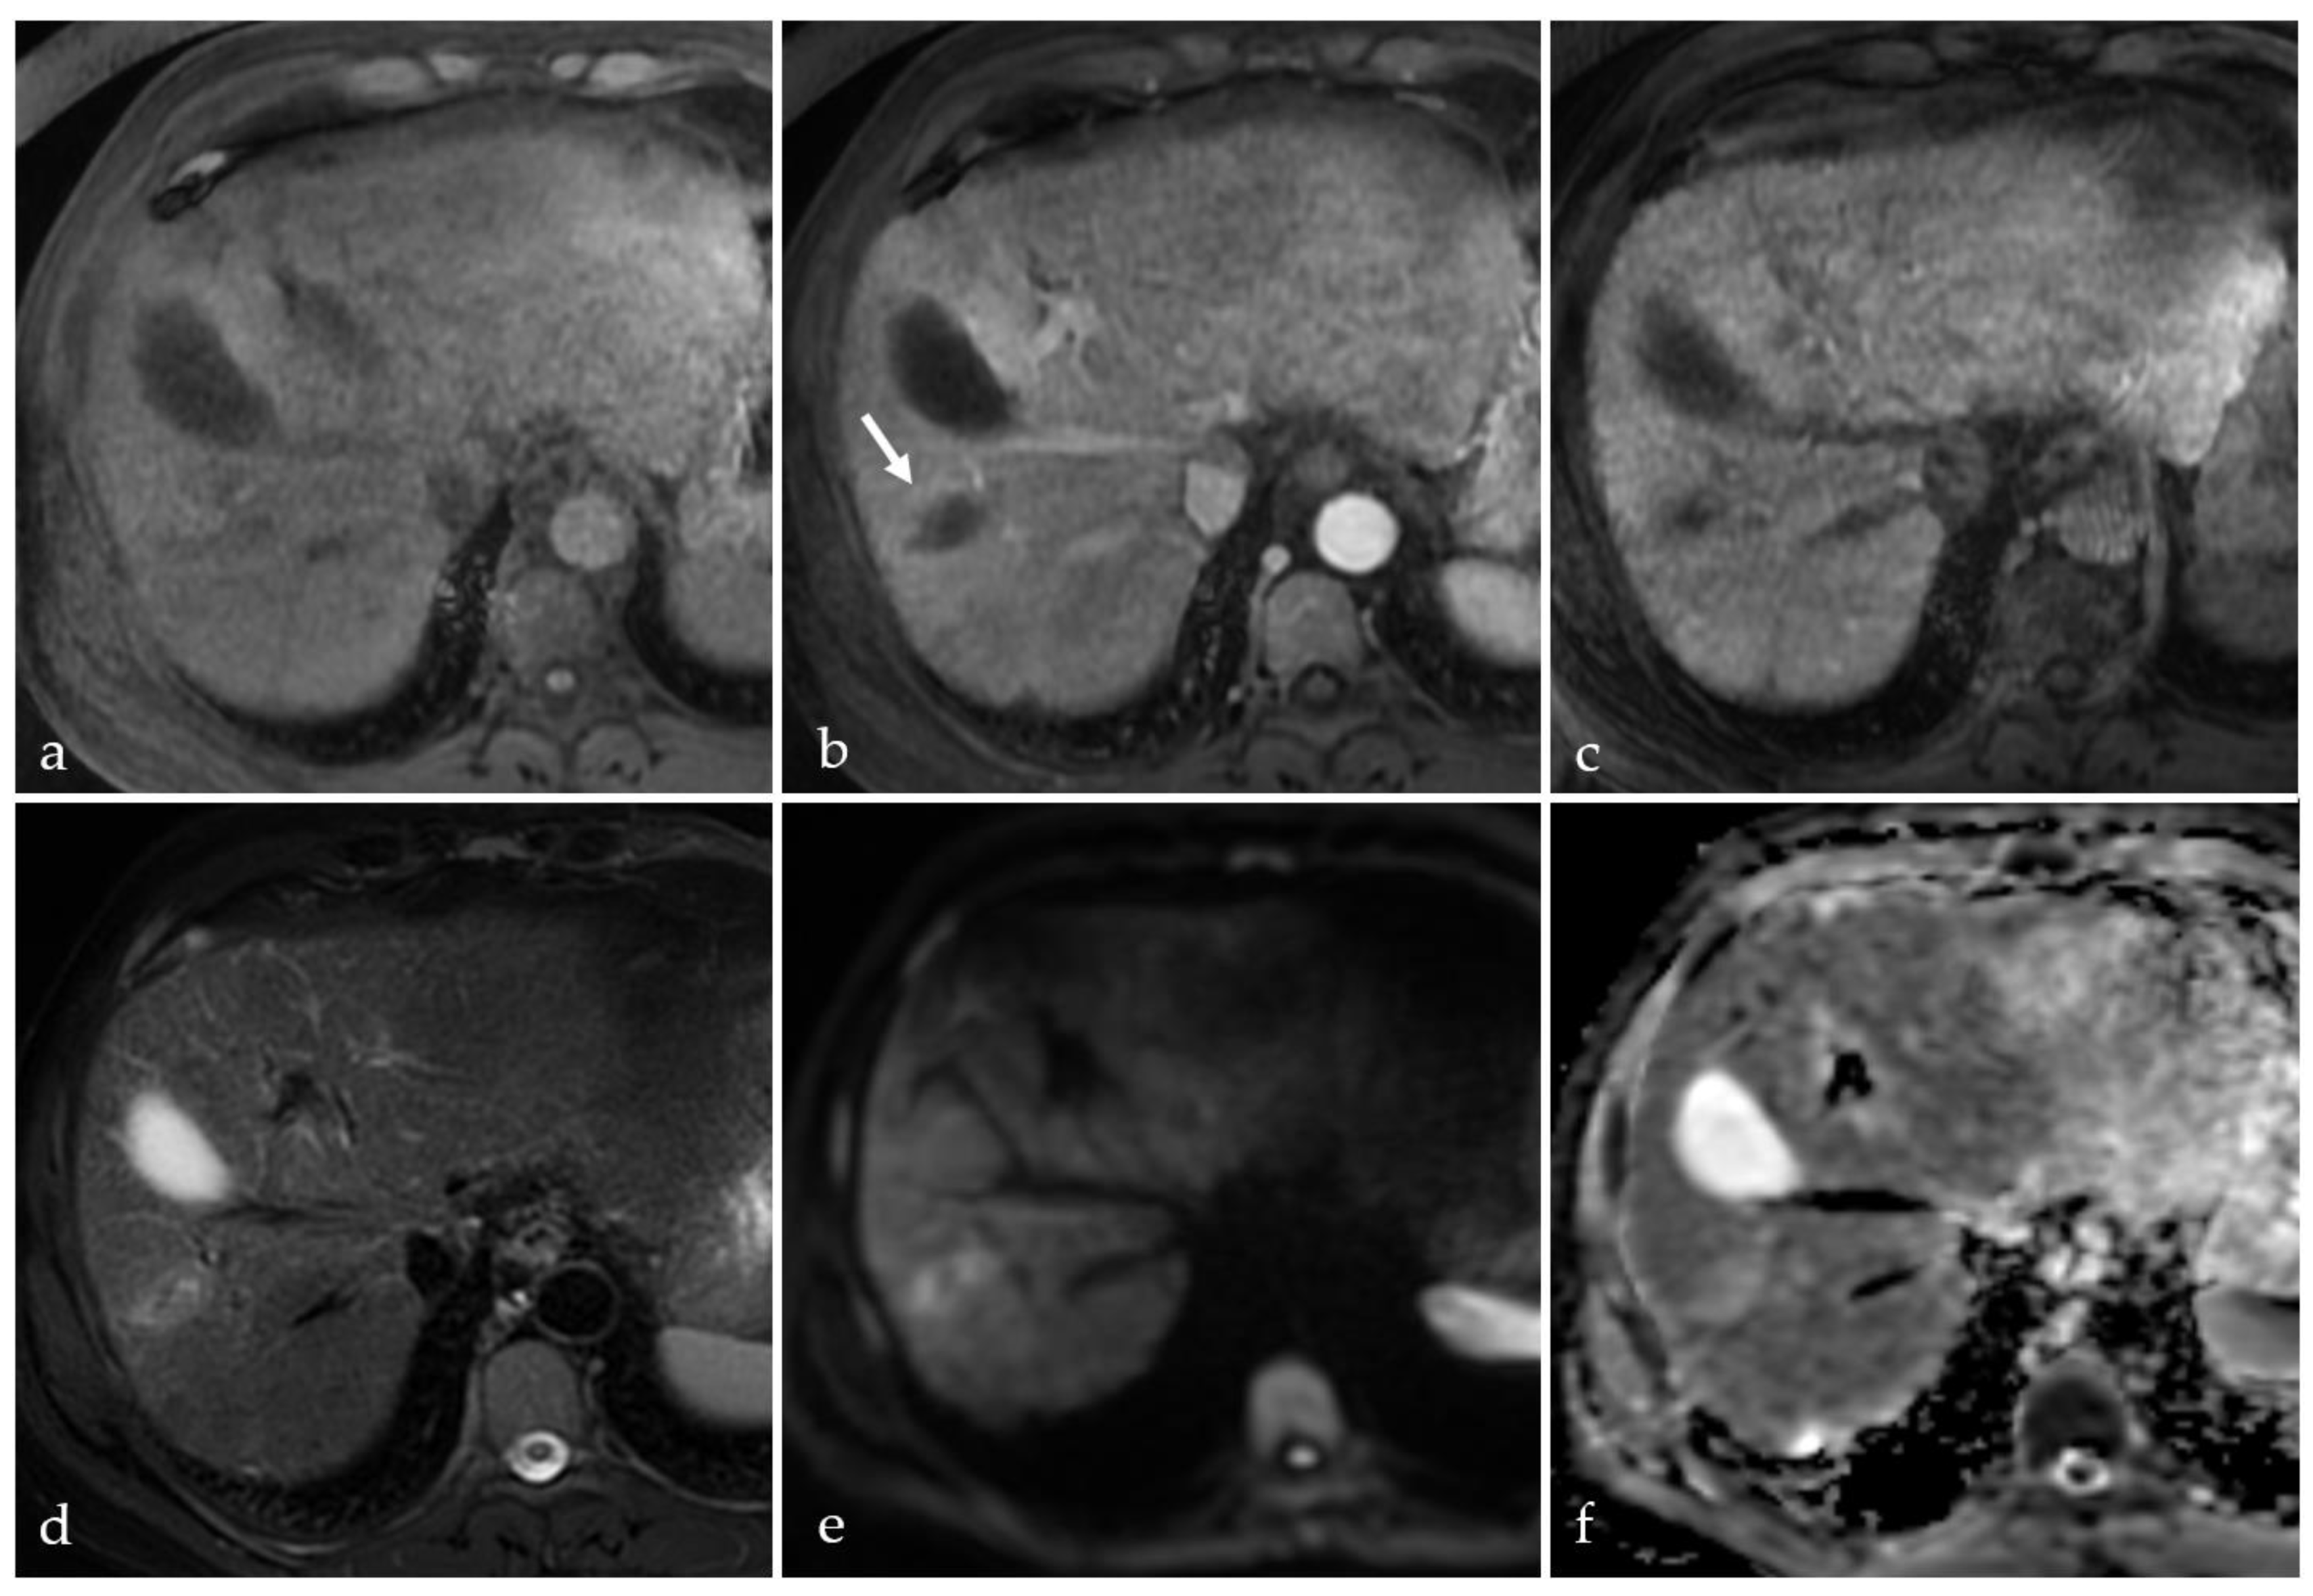

3.4. TACE-Associated Necrosis

3.5. Post-Treatment Imaging Features of Tumor Viability